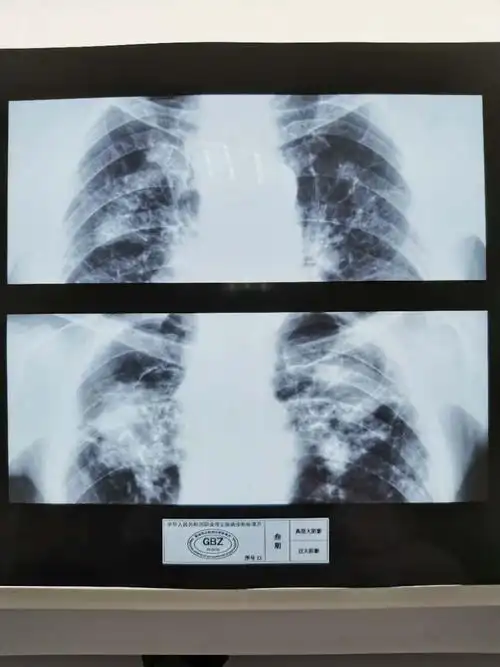

职业病尘肺标准片(照片)